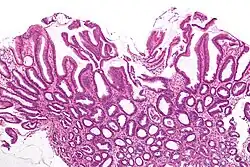

| Micrograph of a reactive gastropathy. H&E stain. | |

- Foveolar hyperplasia (black arrow), as a tortuosity in the "neck" region of the gastric glands.

- Scant or minimal inflammatory cells (white arrow), i.e. lack of large numbers of neutrophils and plasma cells..

- Smooth muscle hyperplasia in the lamina propria (in black oval).

The diagnosis is by examination of tissue, e.g. a stomach biopsy.

Low mag. -